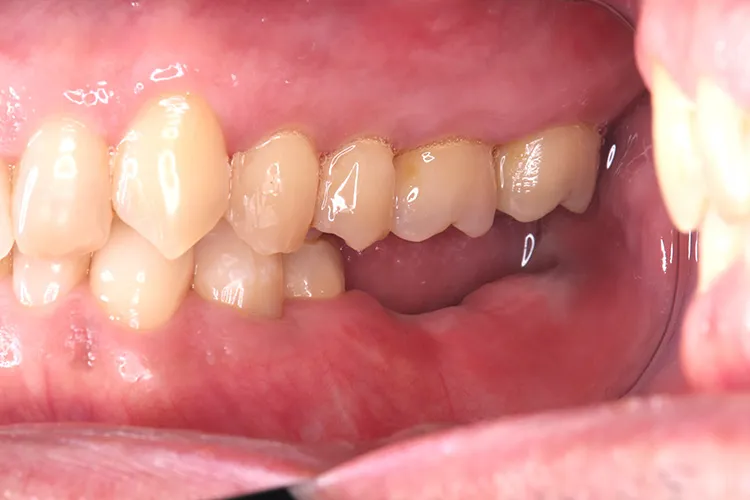

左下の大臼歯の欠損を長期間放置したために上の歯が下がってきてしまい、他の歯医者で被せを入れることができないと断られうちに来られました。下がってきてしまった上の奥歯を部分矯正で上に引っ張り上げ、下に被せ物を入れるスペースを作り、インプラントを入れて噛み合わせを回復しました。部分矯正開始から1年半で治療完了しました。

治療内容

左下67 欠損に対してインプラント治療を行った症例

部分床義歯を使用していたが、どうしても慣れない上にしっかり噛むことができないためインプラント治療を希望